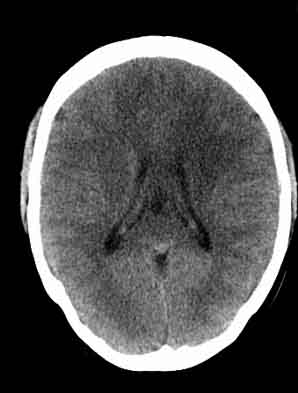

患者,女,29,头痛呕吐2月余,已建议增强或mri进检。

脑沟裂消失,脑白质密度似有减低,考虑脑炎。

左额叶白质密度减低,考虑脑炎,建议增强或mri .

额叶低密度,似炎性改变,mr首选.

双侧脑室前角、旁周围白质低密度减低,边界模糊不清,患者女性:大胆推测,脑白质脱髓鞘改变。mri检查

左侧额叶见低密度影,边界模湖,考虑脑炎, 建议增强除外占位.